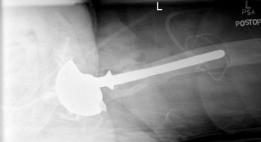

• Augment the cup with multiple screws into stable bone (e.g., ilium, ischium, pubis). ![Image](/media/upload/orthopedic-case-figure-6-31.png)

4. Uncontained Defects (Paprosky Type IIB/IIIA):

• Augments: For superior segmental defects (IIB/IIIA) or column deficiencies, HPM augments (often crescent-shaped or oblong) are invaluable. They are contoured to fit the defect and then secured to the host bone with screws. The main HPM acetabular shell is then implanted, often achieving fixation partly into the augment and partly into host bone.